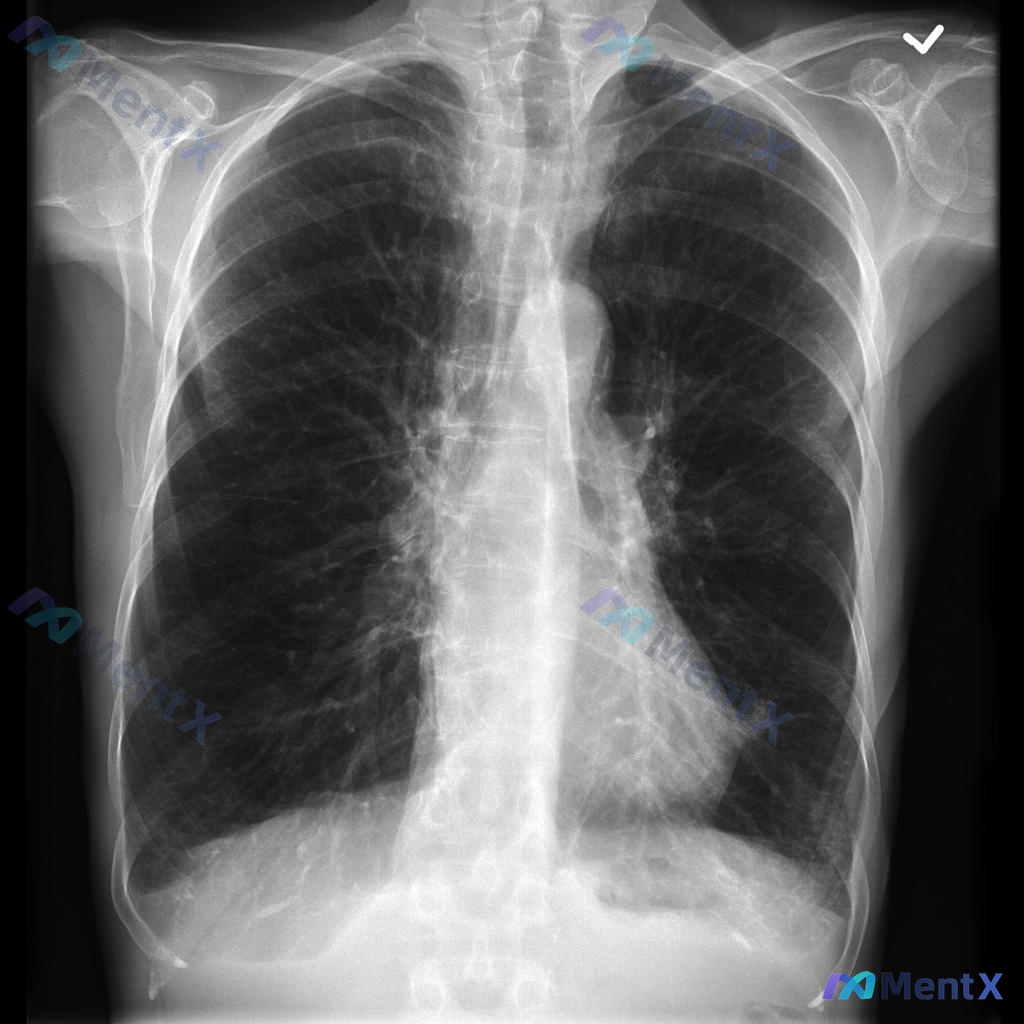

整理了一个呼吸科病例,资料先放在这里: 45岁女性,6个月进行性呼吸短促,爬三楼需要停3-4次,有慢性干咳、喘息,平时用异丙托溴铵吸入,有25包年吸烟史。 查体:生命体征稳定,呼吸26次/分,胸部听诊双侧捻发音,心脏听诊无异常。 动脉血气:pH 7.36,HCO3- 32 mEq/L,Pco2 48...